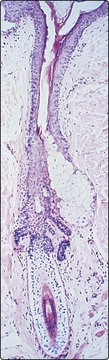

The hair follicle is an invagination of the epidermis containing a hair. The portion above the site of entry of the sebaceous duct is the infundibulum. The hair shaft consists of an outer cuticle that encloses a cortex of packed keratinocytes with (in terminal hairs) an inner medulla (Fig. 1). The germinative cells are in the hair bulb; associated with these cells are melanocytes, which synthesize pigment. The arrector pili muscle is vestigial in humans; it contracts with cold, fear and emotion to erect the hair, producing ‘goose pimples’.

image

Fig. 1 Structure of the hair follicle.